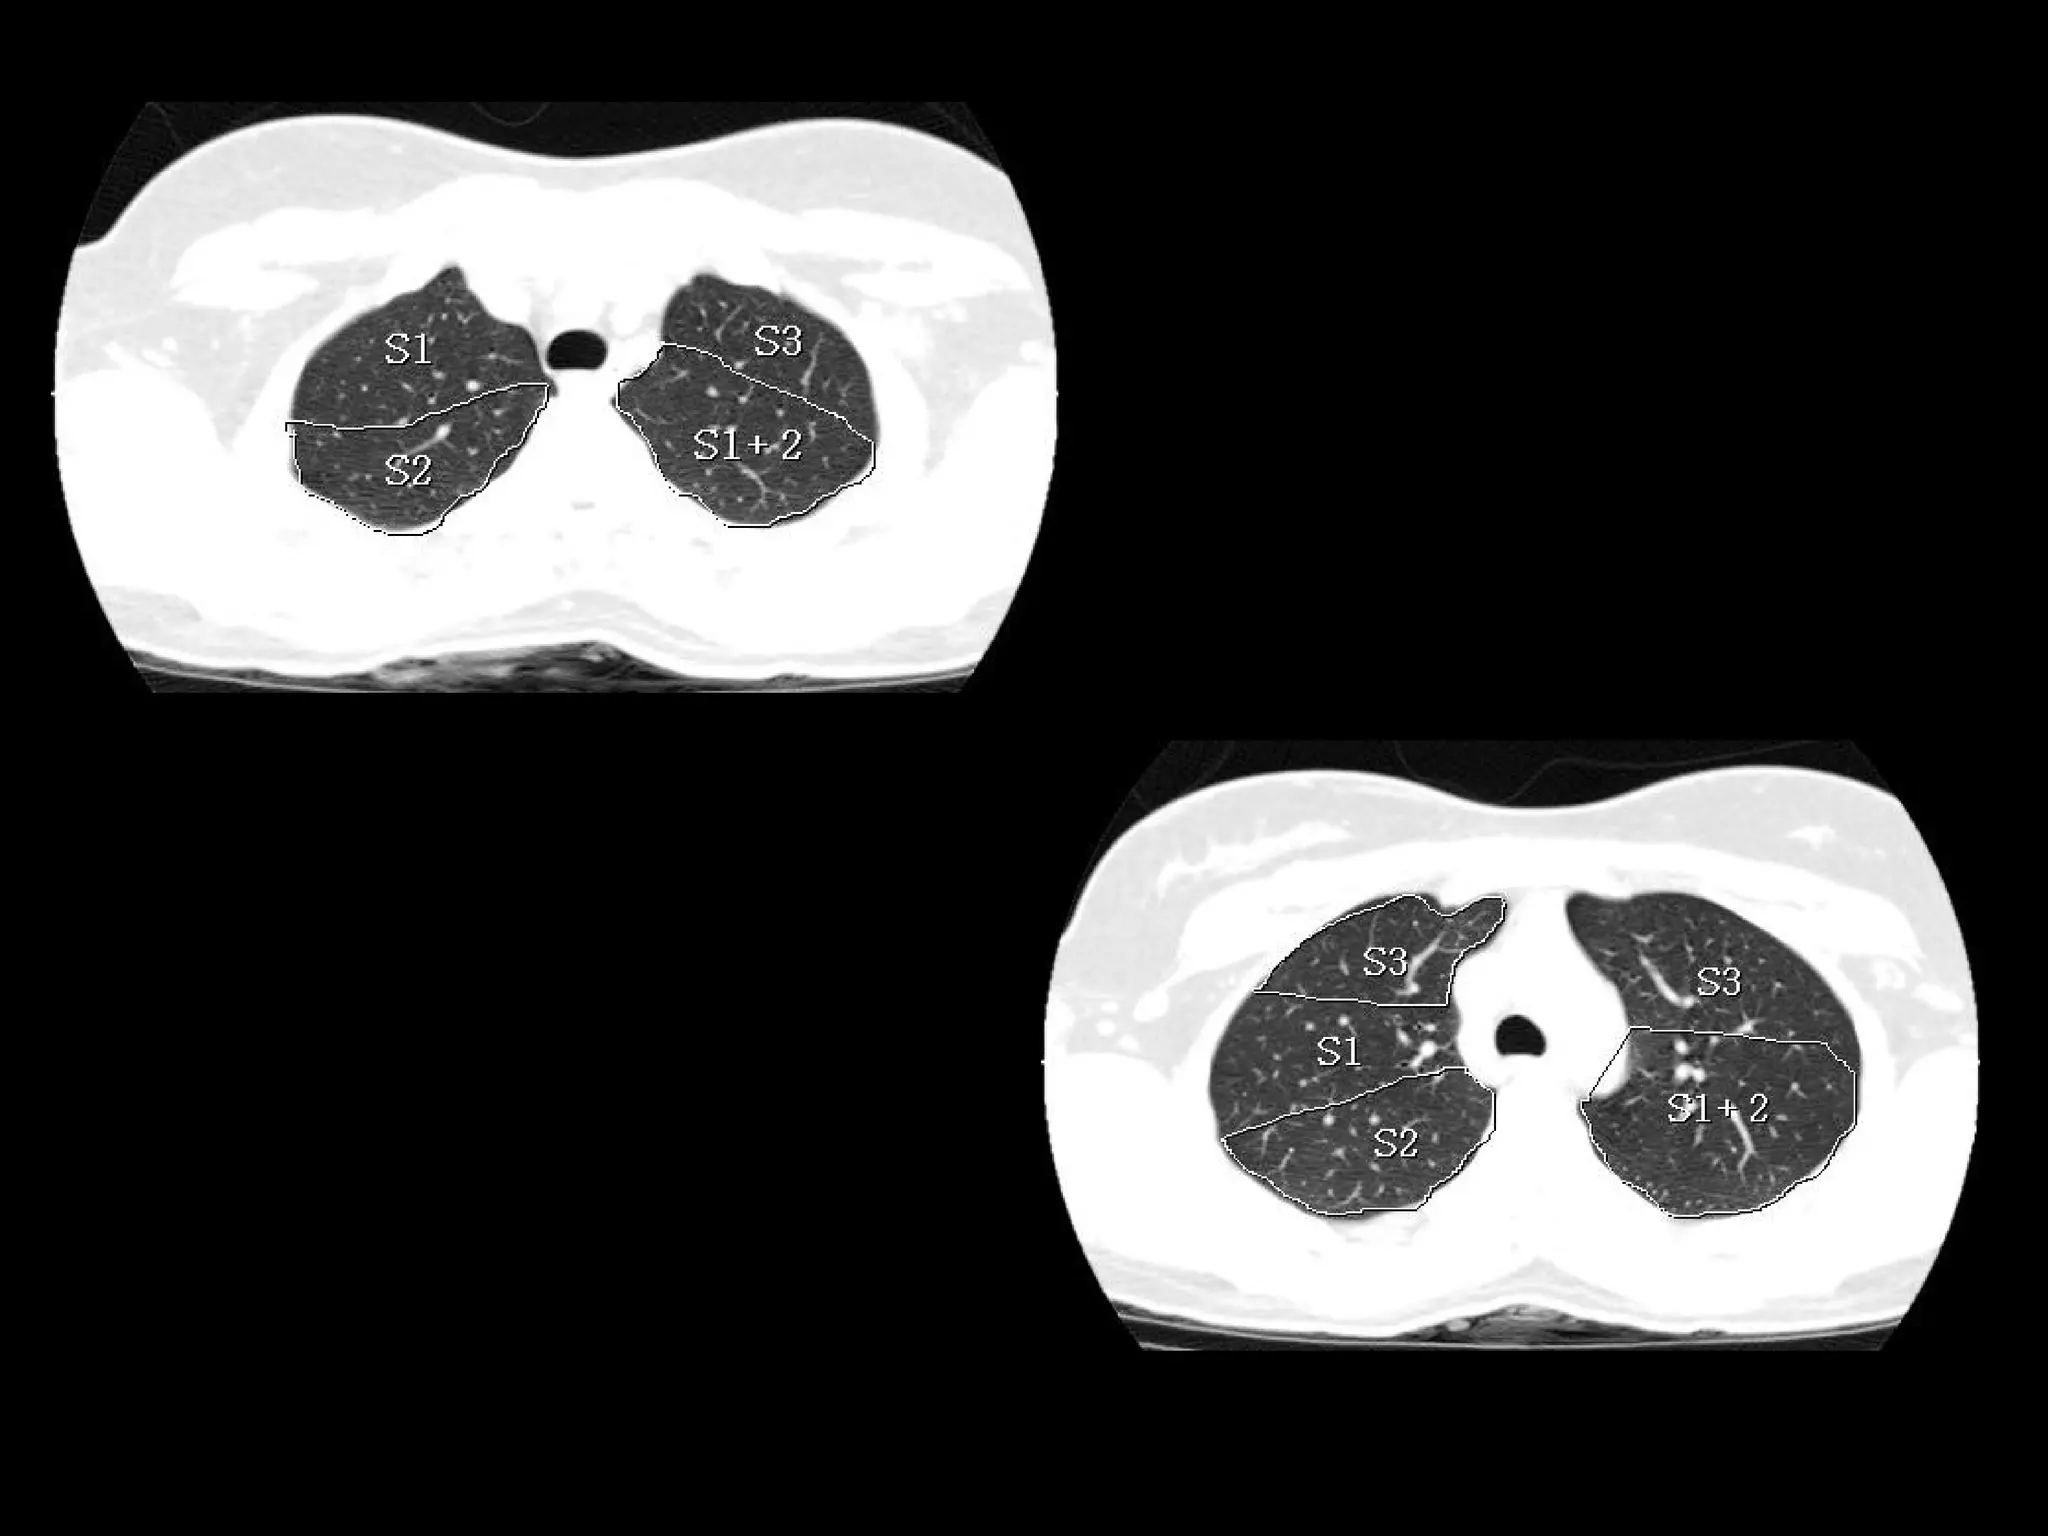

Radiographers are medical professionals who perform diagnostic imaging examinations and procedures to help physicians diagnose and treat diseases. They work under the supervision of radiologists to operate X-ray, CT, MRI, ultrasound and other medical imaging equipment and must have a strong understanding of human anatomy and pathology. Radiographers are responsible for correctly positioning patients, ensuring proper imaging techniques are used, and evaluating the quality of the resulting images.